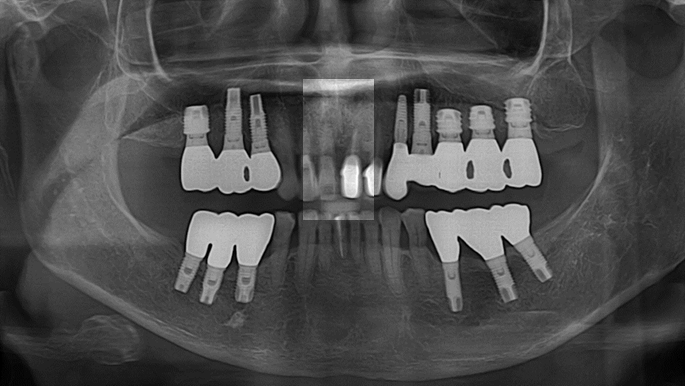

“Automated customized drilling protocols for optimum implant stability/ ONE-DAY implants ”

Clinical case: : Immediate loading of lower molars using R2Gate prefabricated 3D-printed provisional restoration

- Courtesy of Dr. Sam Omar, Egypt -

Dr.Sam Omar, immediate loading, digital guided surgery, digital ONE-DAY implant, maxillary anterior, #21, guided surgery, immediate loading, AnyRidge, R2GATE, Mega ISQ, MEG Torq, R2GATE Full Surgical Kit

implant system, R2GATE Guide, R2GATE surgical kit (AnyRidge), Mega ISQ